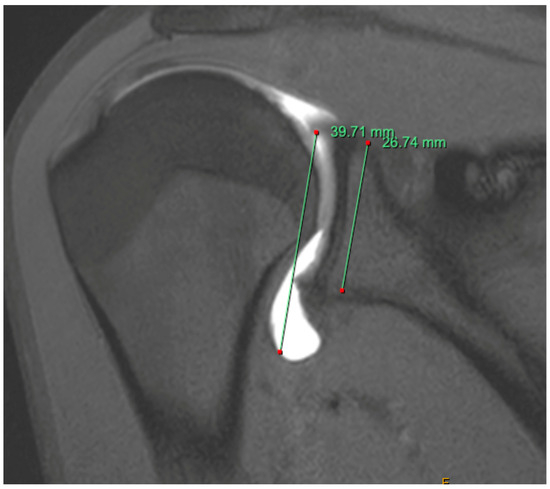

Bone Loss

- Huijsmans, P.E.; Haen, P.S.; Kidd, M.; Dhert, W.J.; van der Hulst, V.P.; Willems, W.J. Quantification of a glenoid defect with three-dimensional computed tomography and magnetic resonance imaging: A cadaveric study. J. Shoulder Elb. Surg. 2007, 16, 803–809. [Google Scholar] [CrossRef]

- Gyftopoulos, S.; Hasan, S.; Bencardino, J.; Mayo, J.; Nayyar, S.; Babb, J.; Jazrawi, L. Diagnostic accuracy of MRI in the measurement of glenoid bone loss. Am. J. Roentgenol. 2012, 199, 873–878. [Google Scholar] [CrossRef]

- Weber, A.E.; Bolia, I.K.; Horn, A.; Villacis, D.; Omid, R.; Tibone, J.E.; White, E.; Hatch, G.F. Glenoid Bone Loss in Shoulder Instability: Superiority of Three-Dimensional Computed Tomography over Two-Dimensional Magnetic Resonance Imaging Using Established Methodology. Clin. Orthop. Surg. 2021, 13, 223–228. [Google Scholar] [CrossRef]